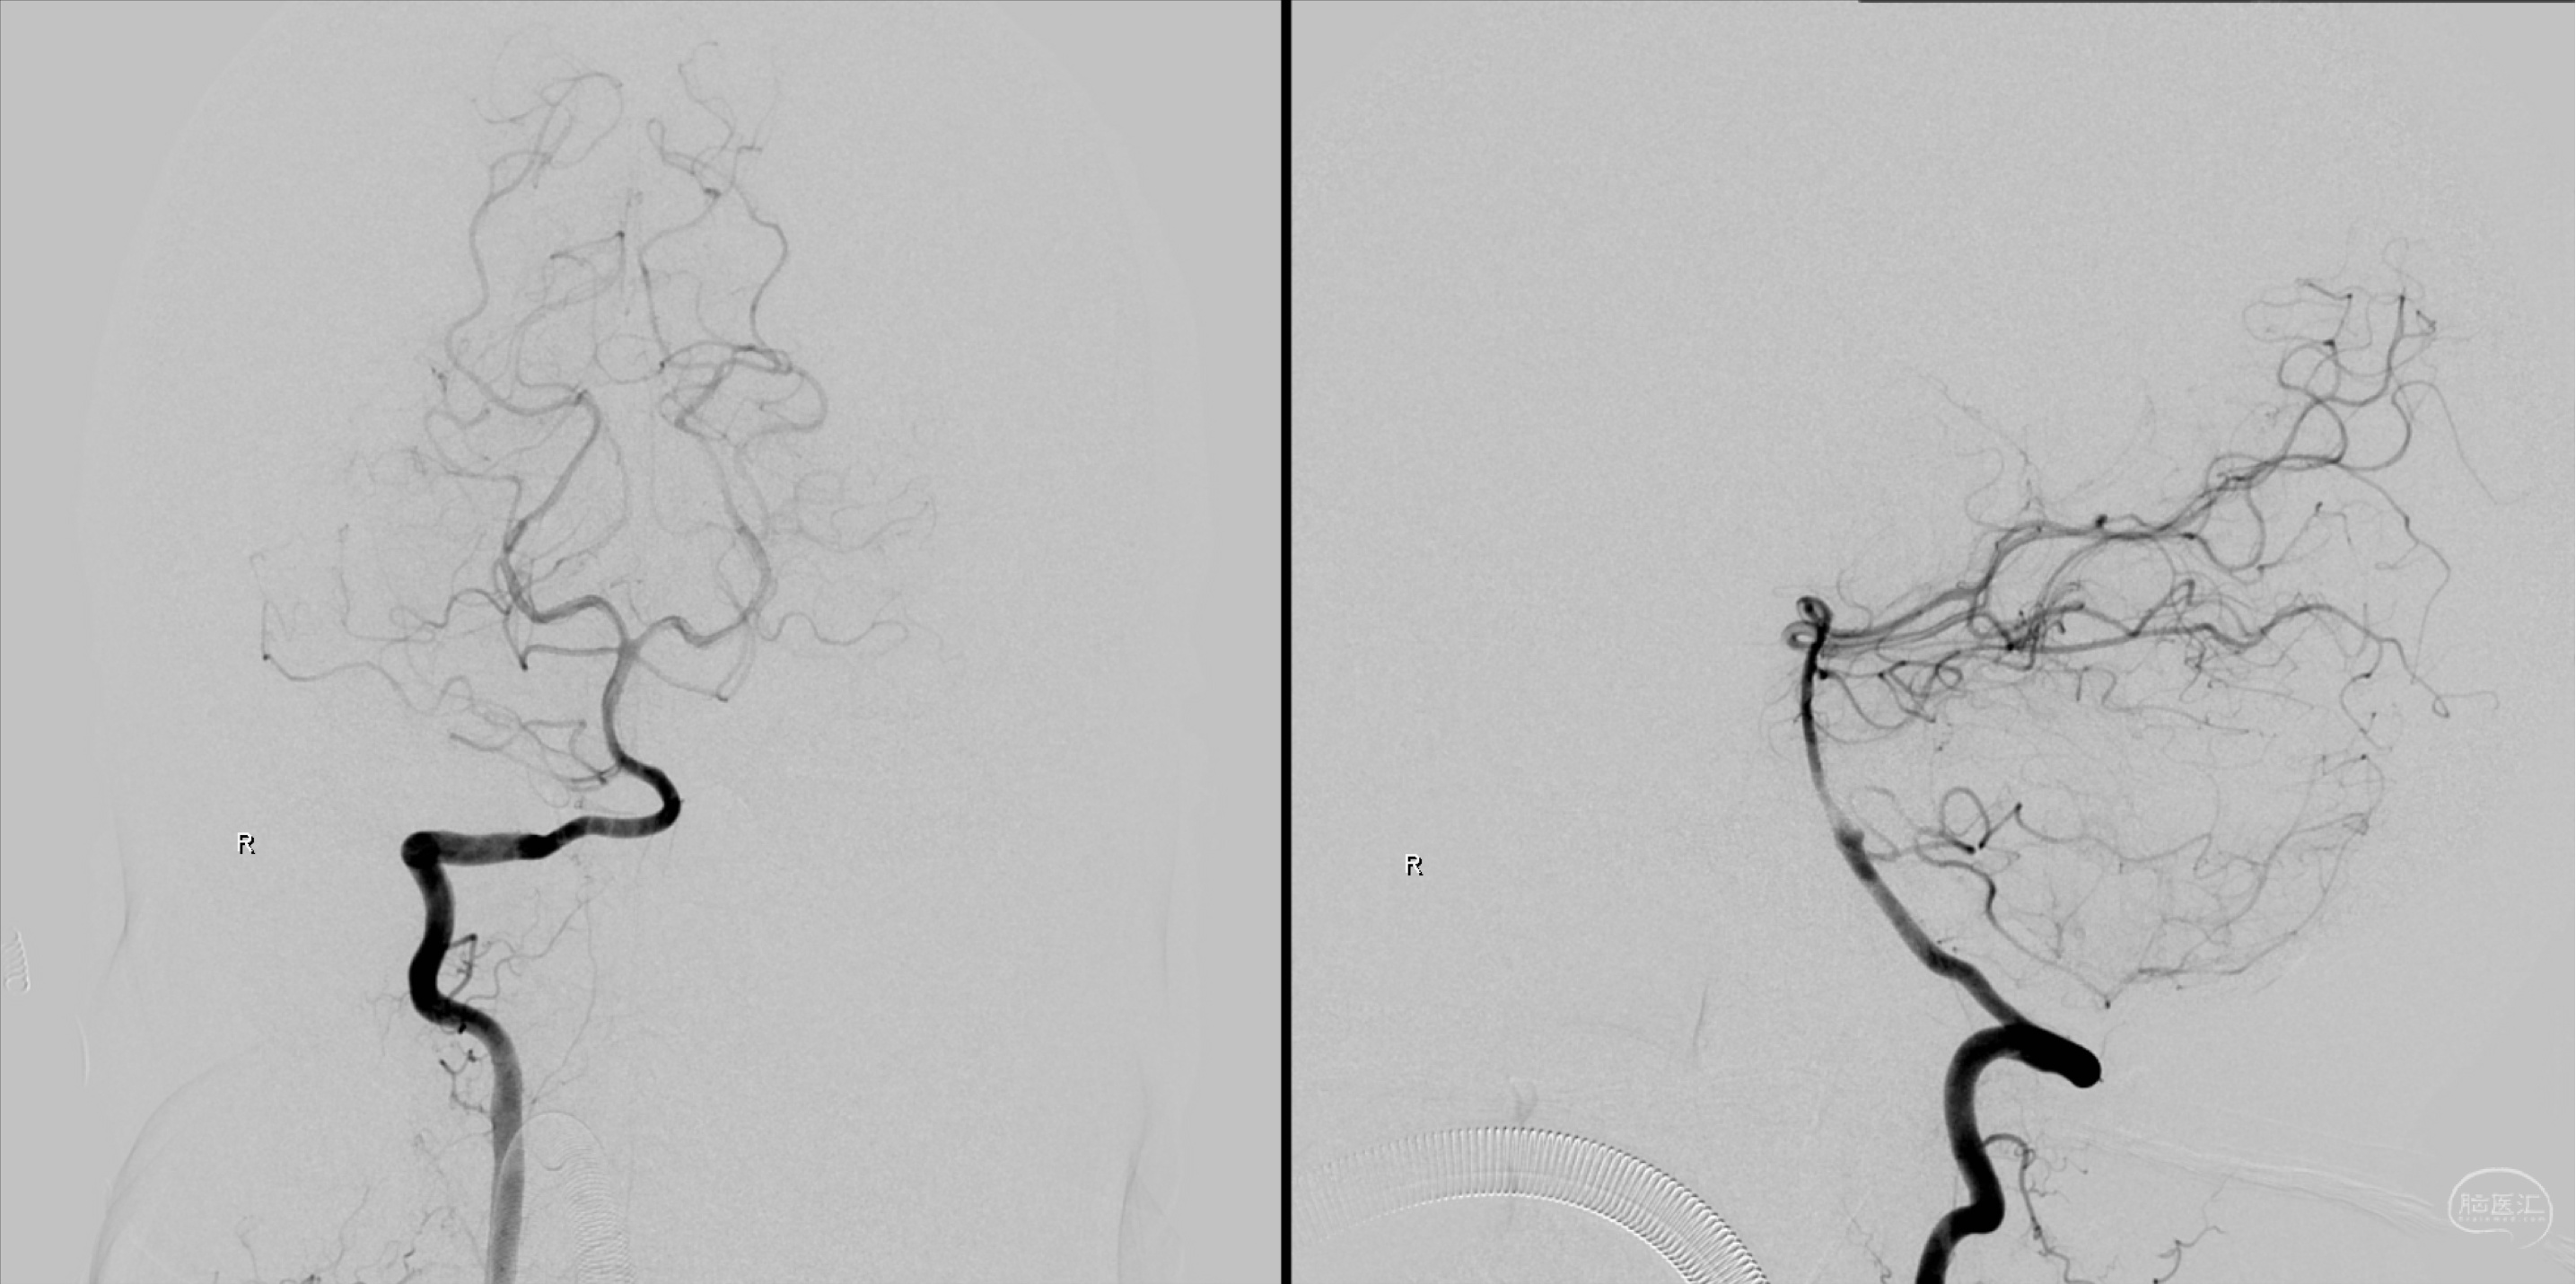

外院全脑血管造影:左侧颈内动脉眼动脉段动脉瘤。

外院左侧颈内动脉正侧位造影:眼动脉段动脉瘤。

外院左侧颈内动脉侧侧位造影:眼动脉段动脉瘤。

右侧颈内动脉正侧位造影:未见明显异常。